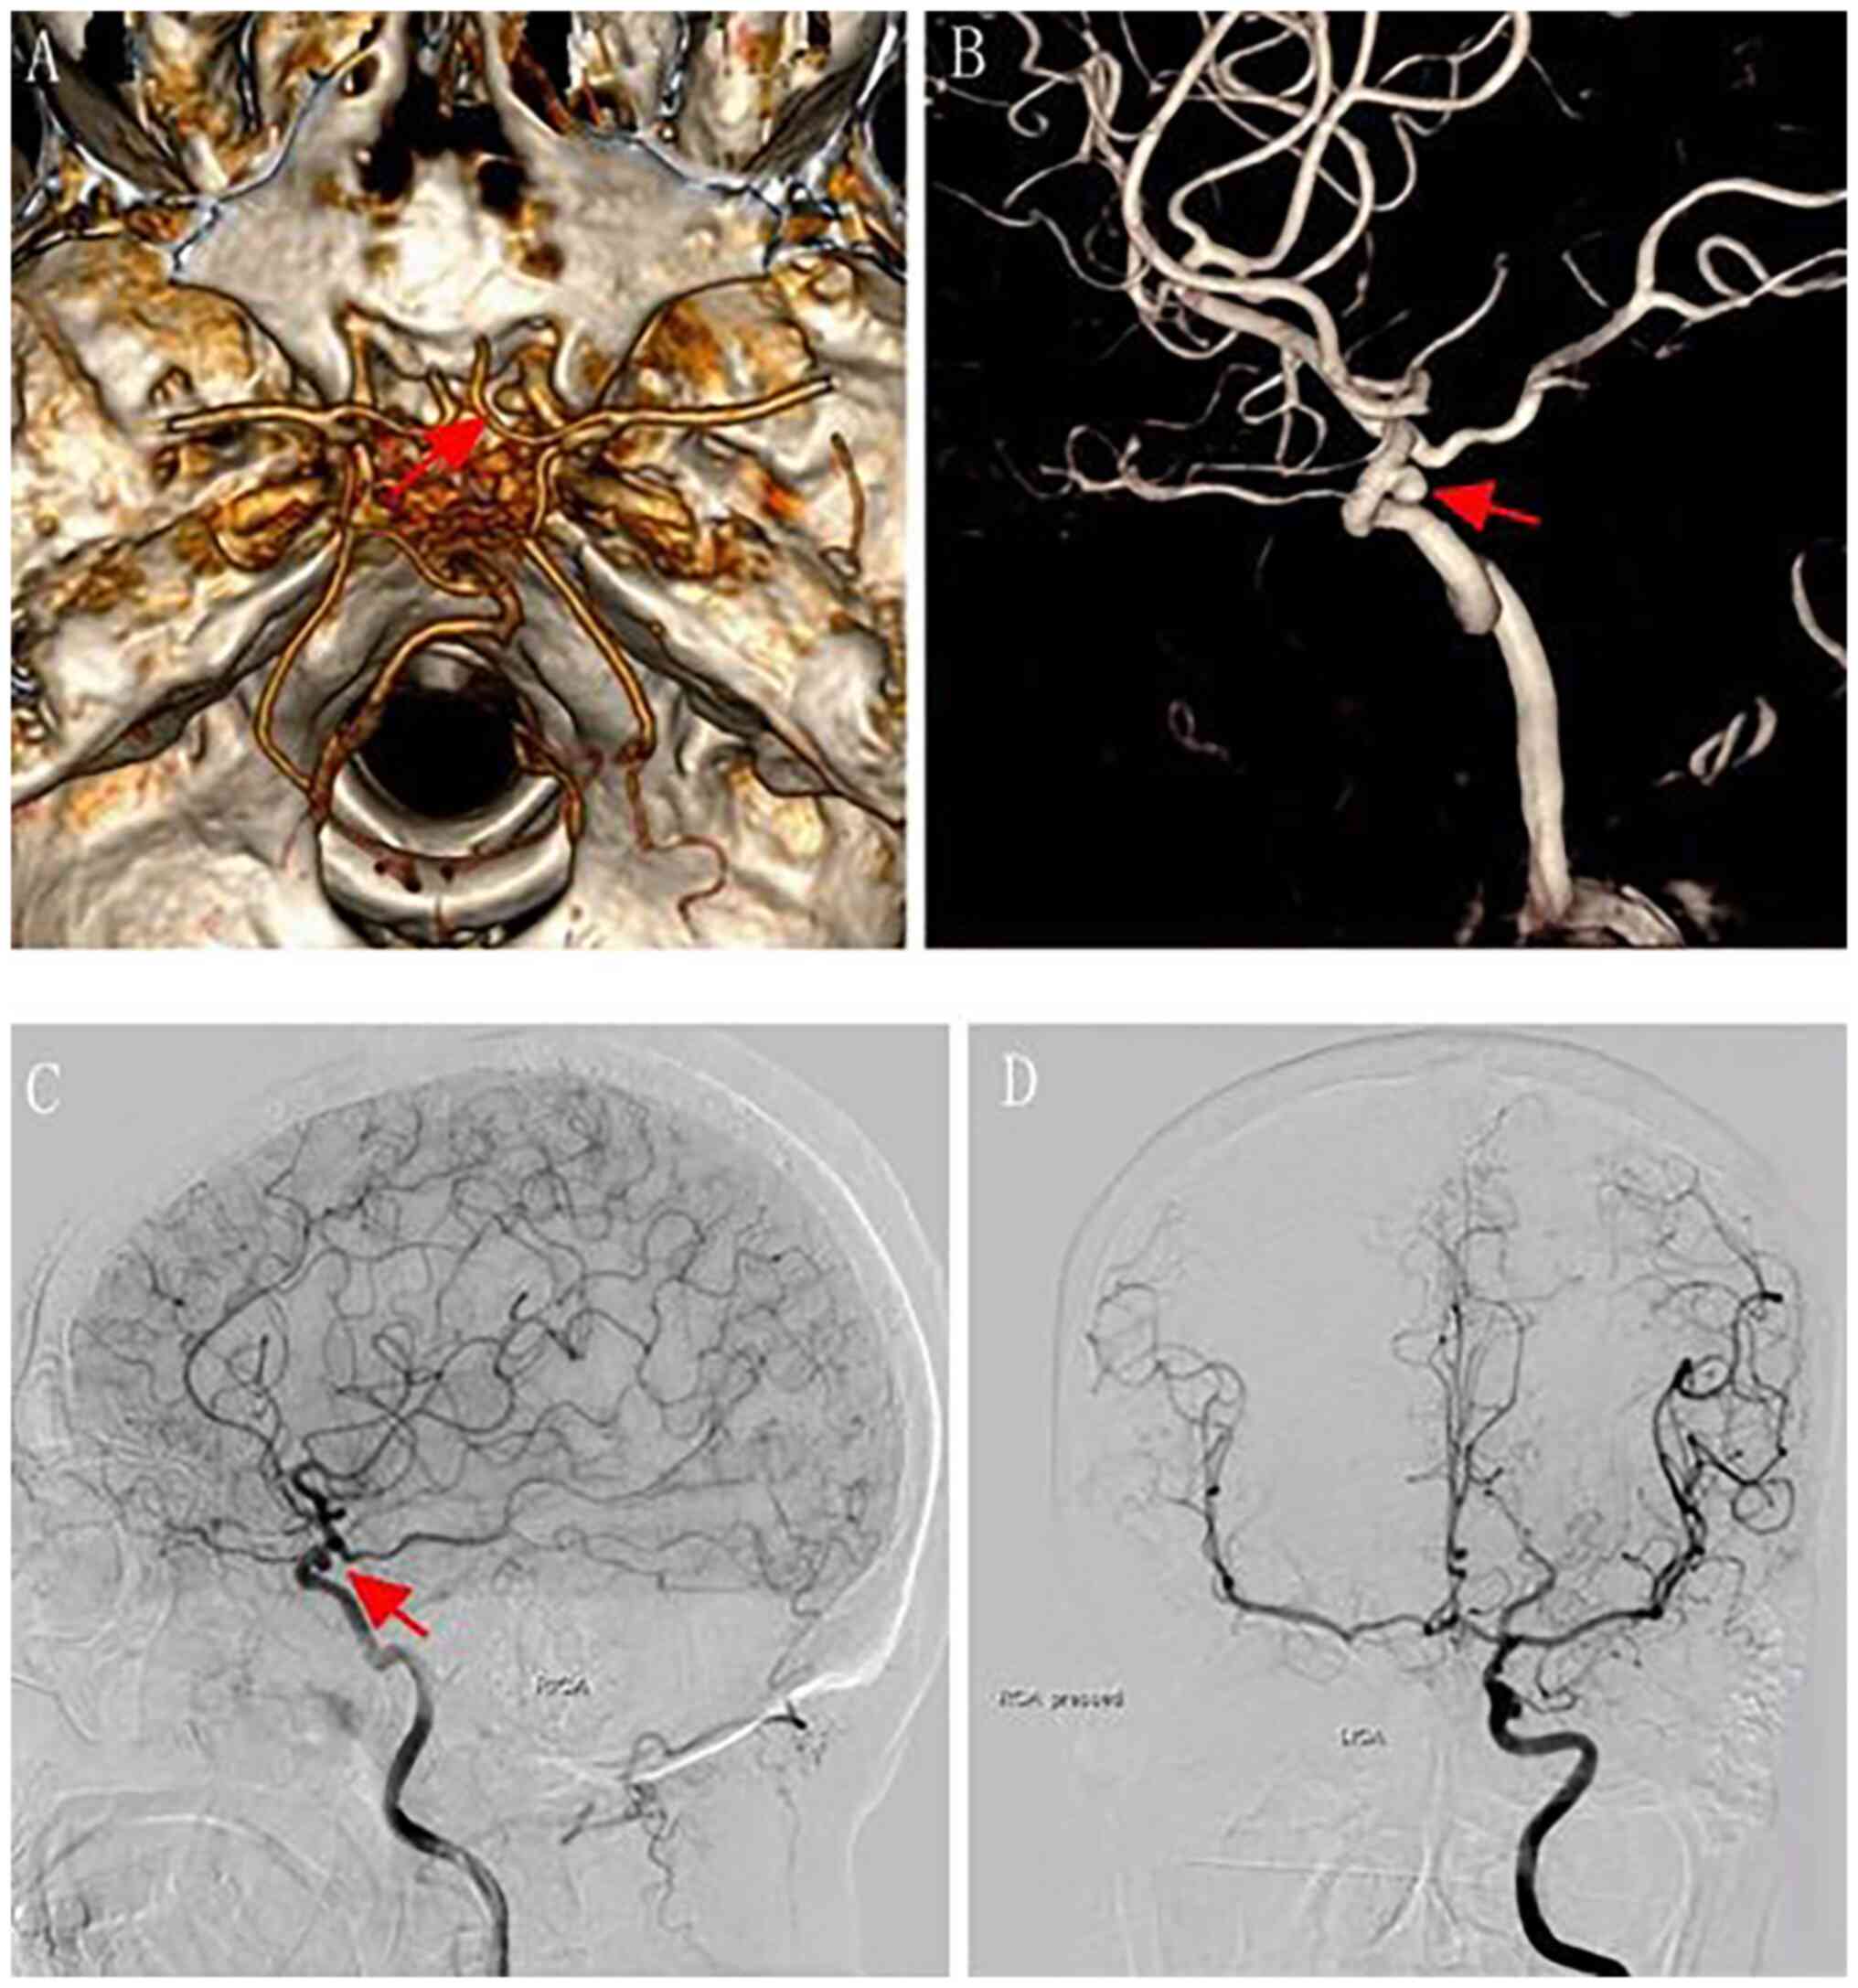

Craniopharyngioma resection and aneurysm clipping performed simultaneously by pure endoscopic endonasal approach: A case report and literature review

Craniopharyngioma is one of the most challenging issues for neurosurgeons as a brain tumor. Among the approaches of neurosurgery, in comparison to craniotomy, the endoscopic endonasal approach (EEA) has risen in popularity over the last two decades; unruptured intracranial aneurysms are relatively commonly found in the general population. The EEA as a new paradigm in the treatment of aneurysm has been reported to successfully clip dozens of cases of intracranial aneurysm. However, when reviewing the domestic and foreign literature, it appeared that cases of craniopharyngioma complicated with intracranial aneurysm purely treated by EEA have not been reported so far. In the present study, the published literature regarding endoscopic endonasal surgery for craniopharyngioma and intracranial aneurysms was reviewed, accompanied with a case of craniopharyngioma complicated with intracranial aneurysm, both of which were simultaneously treated by EEA.